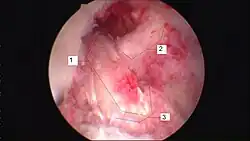

![]() Arthroscopic anterior cruciate ligament (ACL) reconstruction (right knee). The tendon of the semitendinosus muscle was prelevated, folded and used as an autograft (1). It appears through the remnant of the injured original ACL (3). The autograft then courses upwardly and backwardly in front of the posterior cruciate ligament (2). | |